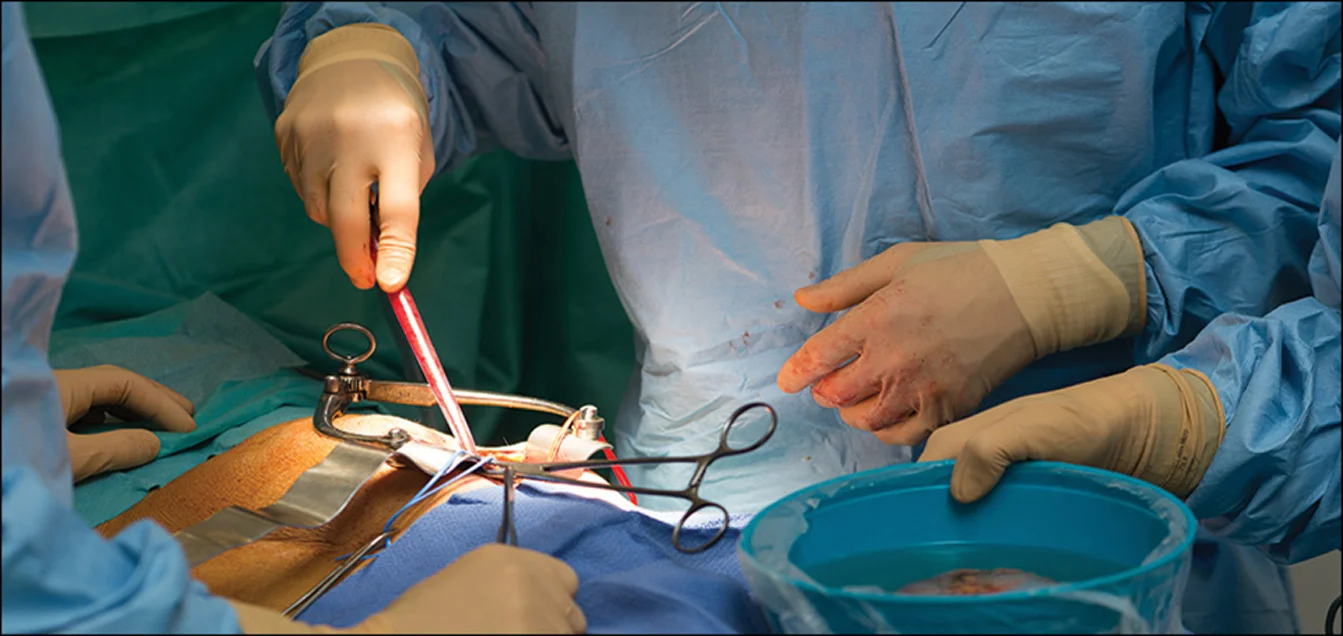

Kidney Transplant

A surgical procedure to replace a failing kidney with a healthy donor organ from a living or deceased donor.